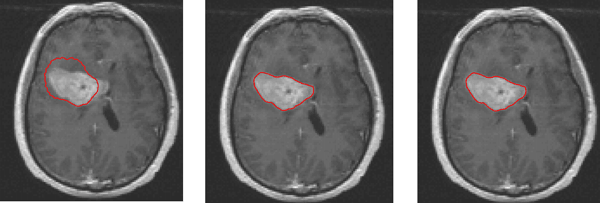

Metode Active Contour, juga dikenal sebagai “Snake,” adalah teknik pengolahan citra yang digunakan untuk mengidentifikasi kontur atau tepi objek dalam citra. Metode ini bekerja dengan mendefinisikan suatu kurva awal di sekitar objek yang diinginkan dan kemudian menggeser kurva tersebut secara iteratif untuk menyesuaikan dengan kontur objek yang sesungguhnya dalam citra. Dalam penelitian ini, metode Active Contour akan diterapkan pada citra MRI otak untuk mengidentifikasi tepi tumor.

Setelah citra MRI diperoleh, langkah berikutnya adalah melakukan segmentasi tumor menggunakan metode Active Contour. Ini melibatkan inisialisasi kurva awal di sekitar tumor dan menggerakkan kurva tersebut hingga sesuai dengan tepi tumor.